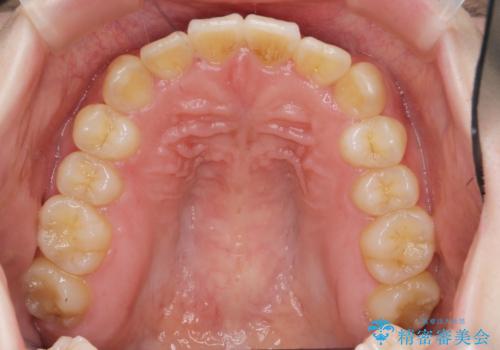

マウスピース矯正では改善の難しい前歯のねじれを前歯の部分ワイヤー矯正で改善したのち、インビザライン矯正を行い歯列を整えます。

インビザラインを行う前に前歯の部分矯正を行ったことで、しっかりとねじれが取れ整った歯列へと仕上げることが出来ました。